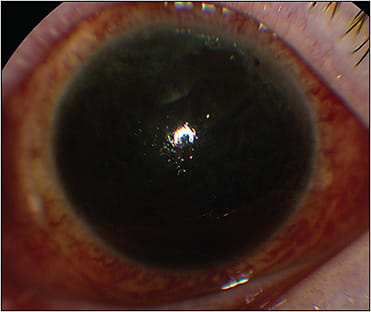

Because a patient on antithrombotics is at high risk from both ocular and systemic perspectives (Figures 1 and 2), it is important for a retina surgeon to have some working knowledge of the indications, management strategies, and pharmacology of commonly used antithrombotic agents. This review aims to provide retina surgeons knowledge and insight enabling them to effectively communicate these complex issues with patients and their medical providers to strive for the best possible outcomes for each patient.

Certain retinal surgeries, such as diabetic vitrectomy with extensive fibrovascular membranes, sutured IOL, scleral buckle with external drainage of subretinal fluid, chorioretinal biopsy, submacular surgery, surgery for hemorrhagic complications of peripheral exudative hemorrhagic chorioretinopathy, and proliferative vitreoretinopathy surgery involving large retinectomies may be at particularly high risk for perioperative bleeding (Figures 1 and 2). Other ocular factors that increase the risk of perioperative bleeding including suprachoroidal hemorrhage include myopia, glaucoma, inflammation, and hypotony.34,35